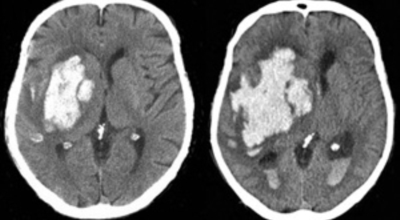

뇌출혈 전조증상을 살펴보기에 앞서 뇌출혈이란 구체적으로 무엇인지 알아보겠습니다.우리 신체의 구조상 뇌는 산소를 저장할 수 없게 되어 있어요. 그렇다면 어떻게 필요한 산소를 공급받을 수 있을까요? 우리 뇌는 산소와 영양분을 공급받기 위해 우리 몸의 구석구석을 누비는 혈관에 의존해 도움을 받습니다.

만약 이런 혈관이 파열되고, 공급되던 산소가 누출되어 뇌 조직에 도달하지 못하면 어떻게 될까요? 혈액이 고이며 뇌에 부담(압력)을 주며, 응급조치가 없이 3~4분 이상 산소가 결핍된 상태가 지속되면 뇌세포는 죽습니다. 그러면 함께 영향을 받는 신경 세포가 제어능력을 잃게 되고, 우리 몸의 기능도 함께 손상되는 것으로 보입니다.